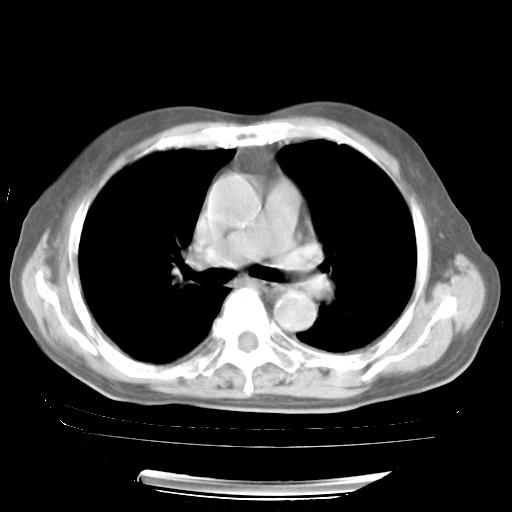

4月28日肺部CT——再次出现类似去年5月9日——透光度降低,“间质性”改变。

4月28日肺部CT——再次出现类似去年5月9日——磨玻璃样、间有“粟粒样”改变。

4月28日肺部CT